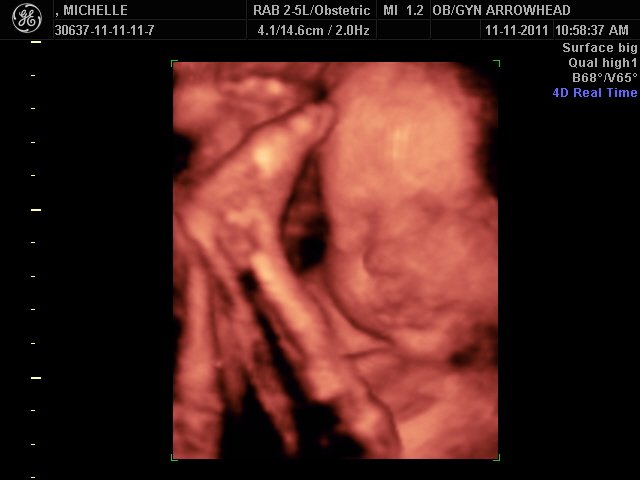

We offer complimentary 3D/4D Ultrasounds to all our OB patients around 30 weeks! The following photos are some examples of our work, shown with permission from our patients.